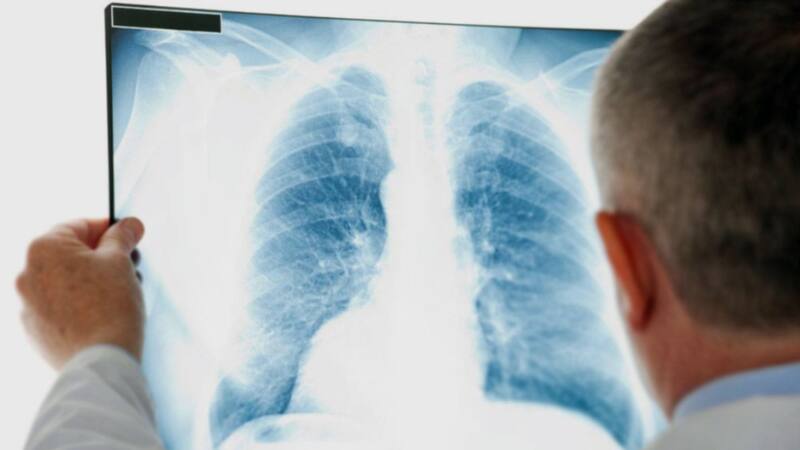

El radiólogo es un médico especialista encargado de elaborar un diagnóstico clínico a través de las distintas modalidades de imagen, que incluyen los rayos X (de donde viene el nombre de la especialidad, a pesar de que actualmente constituye menos del 10% de su actividad), ultrasonido, tomografía computada y resonancia magnética. Estas técnicas de imagen permiten además guiar procedimientos diagnósticos y terapéuticos percutáneos mínimamente invasivos reemplazando técnicas quirúrgicas.

Según la OMS, se estima que un 80% de las decisiones médicas se toman con el apoyo de la Radiología, haciendo del radiólogo un integrante crucial del equipo médico. Los avances tecnológicos han permitido desarrollar estudios de mejor calidad con menor riesgo para el paciente, disminuyendo las dosis de radiación y tiempos de estudio, permitiendo diagnósticos más oportunos y certeros.

Así, la tecnología ha impulsado a la radiología de manera extraordinaria, como por ejemplo, para el hallazgo de lesiones traumáticas, detección temprana de muchas neoplasias como cáncer de mama, próstata, pulmón, páncreas, renal, entre otras. Prácticamente todas las especialidades de la medicina actual se han visto beneficiadas con esta especialidad y gran parte de sus diagnósticos se basan en la opinión del radiólogo.